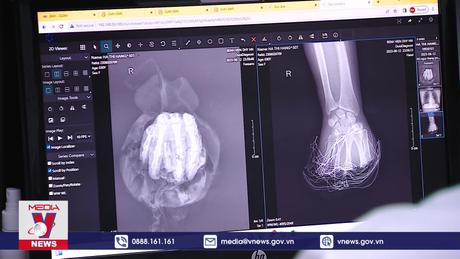

Bệnh viện Đức Giang (Hà Nội) vừa phẫu thuật thành công bóc tách khối u phổi nặng 3 kg ra khỏi lồng ngực nữ bệnh nhân 71 tuổi.